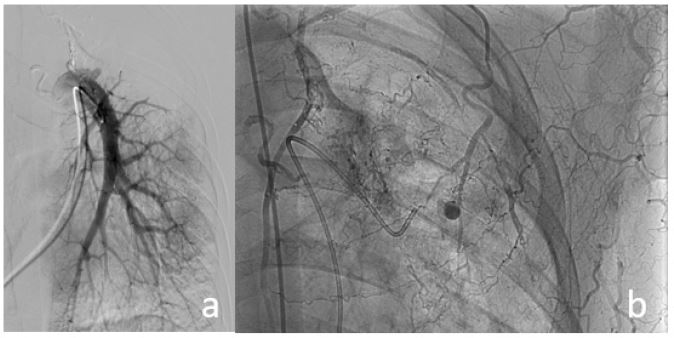

A 39-year-old male with a history of discontinued pulmonary tuberculosis treatment one year prior was admitted for hemoptysis. A few days before admission, he experienced intermittent episodes of hemoptysis, with the most significant bleeding estimated at 30-50 mL. No treatment had been initiated at that time. Chest Computed Tomography (CT) revealed a cavitary consolidation in the left upper lobe, with a 5 × 4 mm pseudoaneurysm located at the peripheral wall of the cavity. There was also evidence of a dilated left bronchial artery and hypertrophied intercostal and subclavian artery branches.

Figure 1: Cavitary consolidation in the left upper lobe. A 5 × 4 mm pseudoaneurysm is seen within the cavity wall (arrow). Dilated bronchial artery, along with hypertrophied and dilated left intercostal and subclavian artery branches, are also noted.

In our case, the patient underwent contrast-enhanced 64-slice chest CT with multiplanar reconstructions. Imaging revealed a cavitary consolidation in the left upper lobe, with a 5 × 4 mm pseudoaneurysm located in the cavity wall, along with dilation and hypertrophy of the left bronchial artery, intercostal branches, and the left subclavian artery. This underscores the vital role of CT imaging in evaluating patients with hemoptysis, particularly for identifying pulmonary vascular lesions.